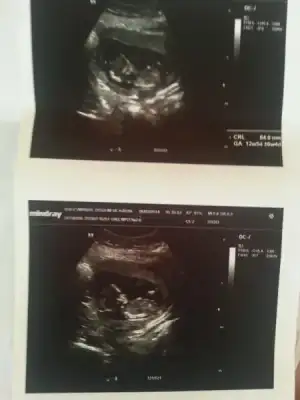

dr soylemeden siz gorun genital nub teorisi ( bebegin cinsiyeti)

Selam kizlarr doktordan geldim bebisim tam 15 haftalik olmus. Sagligi kemiknyapisi vs hersey sagligkli gizukuyo masallah:nazar:

Zeynebimm defneee cinsiyet beli oldu tahminleriniz doru ciktii